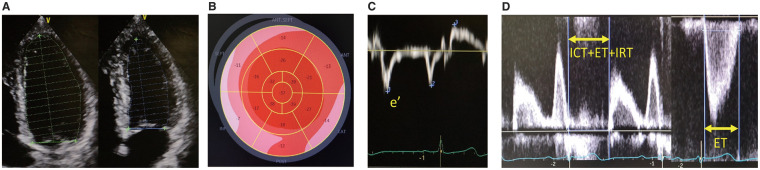

Methods and results: Between 2021 and 2024, we included 81 patients who underwent transfemoral TAVR for severe AS. We used the natural logarithm of B-type natriuretic peptide (lnBNP) 1 week after TAVR as an indicator of the early effects on LV mechanics. To determine the association with echocardiographic parameters (LV ejection fraction [LVEF], global longitudinal strain [GLS], E/e', and Tei index) and postprocedural lnBNP, we used regression models while adjusting for covariates. There were no significant differences in LVEF, GLS or E/e' between before and after TAVR, but the postprocedural Tei index was significantly higher than the preprocedural Tei index (0.40 vs. 0.26, P<0.01). In a univariate linear regression, the preprocedural LVEF (β=-0.28, P=0.01), GLS (β=-0.24, P=0.04), E/e' (β=0.36, P<0.01), and Tei index (β=0.27, P=0.02) correlated with postprocedural lnBNP. Regarding the postprocedural parameters, GLS (β=-0.27, P=0.02) and E/e' (β=0.36, P<0.01) also correlated with postprocedural lnBNP, but the LVEF and Tei index did not. After adjustment for covariates, these correlations remained significant.

Conclusions: Preprocedural echocardiographic parameters reflecting LV function correlated with BNP after TAVR, but the utility of postprocedural parameters may depend on preprocedural LV function or perioperative factors.